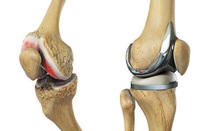

Trong ca phẫu thuật được thực hiện với sự giám sát của các bác sĩ phẫu thuật chỉnh hình, robot đã thay thế khớp gối cho một bệnh nhân 73 tuổi tại Bệnh viện Đại học Tứ Xuyên.

Ông Zhou Zongke, Giáo sư chỉnh hình thuộc Bệnh viện Đại học Tứ Xuyên, cho biết bệnh nhân đã bị đau gối hơn 10 năm qua và được chẩn đoán viêm khớp gối. Theo vị giáo sư này, trước khi thực hiện ca phẫu thuật có sự tham gia của robot trên, các bác sĩ đã đưa dữ liệu chụp cắt lớp đầu gối của bệnh nhân vào một máy tính để mô phỏng và xem trước tiến trình phẫu thuật trên máy tính.

Giáo sư Zhou Zongke cho biết robot rất thông minh và thực hiện các thao tác có độ chính xác cao về định lượng, góc cắt và độ dày mặt cắt. Ngoài ra, vết mổ nhỏ hơn so với vết mổ thực hiện bằng phương pháp truyền thống.

Đau khớp gối là bệnh rất phổ biến ở người già, đặc biệt là các bệnh nhân khoa chỉnh hình. Các bác sĩ sẽ quyết định sử dụng robot hỗ trợ các cuộc phẫu thuật ở người tùy theo tình trạng của mỗi bệnh nhân.